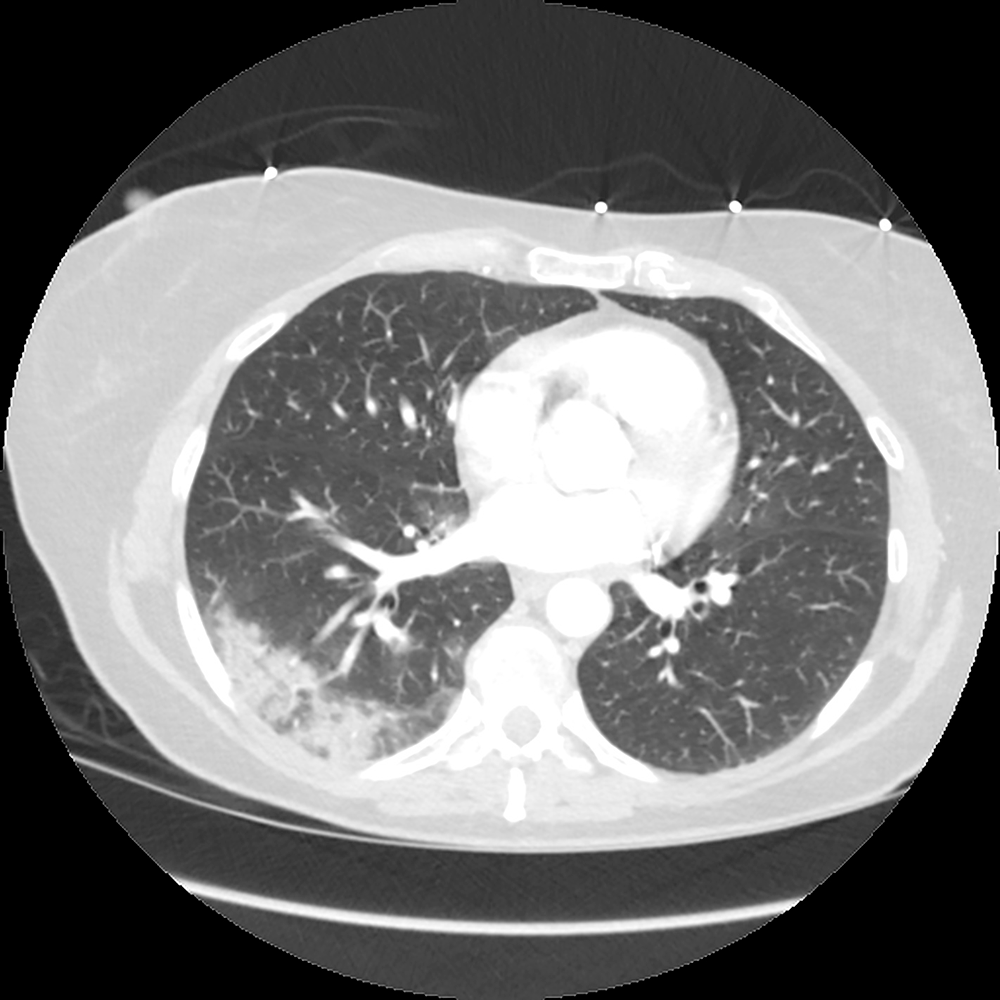

Moderately/severely symptomatic patients: CXR is often negative early, only to turn positive subsequently. The most characteristic findings are basilar and peripheral ground-glass opacities (GGOs) (Fig. 1).

Unfortunately, only a minority of patients have this typical COVID-19 pattern. In most patients, the disease is located more diffusely or elsewhere. Consolidation may be present initially with more severe illness or duration (Fig. 2).

Early on, CT may be positive when the CXR is negative. The typical GGO distribution is similar, but usually more extensive than on CXR (Fig. 3).